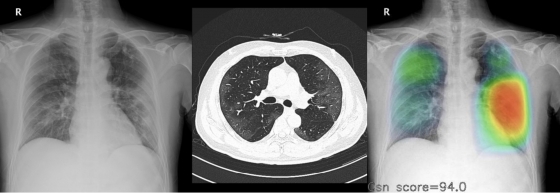

| ¡ã(¿ÞÂʺÎÅÍ) Äڷγª19 È®ÁøÆÇÁ¤À» ¹ÞÀº ȯÀÚÀÇ ÈäºÎ ¿¢½º·¹ÀÌ, CT, AI ºÐ¼® »çÁø |

·ç´Ö ÀλçÀÌÆ® CXRÀº ÀΰøÁö´ÉÀÌ È¯ÀÚÀÇ ÈäºÎ ¿¢½º·¹ÀÌ »çÁøÀ» ¼ö ÃÊ ³»·Î ºÐ¼®ÇØ, °¢ Áúȯ ÀÇ½É ºÎÀ§¿Í ÀÇ½É Á¤µµ¸¦ »ö»ó µîÀ¸·Î ÀÚµ¿ Ç¥±âÇÏ´Â ¹æ½ÄÀÌ´Ù. ȯÀÚÀÇ ¾çÂÊ Æó¿¡ Á¸ÀçÇÏ´Â º´º¯À» Á¤È®ÇÏ°Ô ³ªÅ¸³ÂÀ½À» È®ÀÎÇÒ ¼ö ÀÖ´Ù.

·ç´Ö ÀλçÀÌÆ® CXR º¸Á¶·Î Äڷγª19 ÀÇ½É È¯ÀÚµéÀÇ ÈäºÎ ¿¢½º·¹À̸¦ ÆÇµ¶ÇÒ °æ¿ì, (À§ÂʺÎÅÍ) PCR °Ë»ç¸¦ ÅëÇØ Äڷγª19 È®ÁøÀ» ¹ÞÀº ȯÀÚ´Â 68.8%ÀÇ °ËÃâÀ²À», Æó·ÅÀ» µ¿¹ÝÇÑ ¾ç¼º µ¥ÀÌÅÍ È¯ÀÚ´Â 81.5%ÀÇ °ËÃâÀ²À» º¸¿´´Ù.